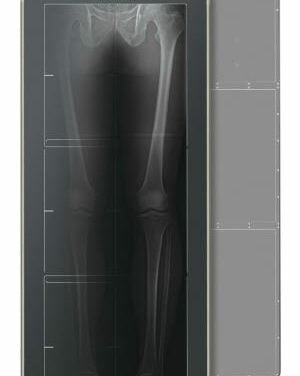

Fujifilm Medical Systems will showcase its FDR D-Evo GL DR detector for single-exposure, long-length digital imaging at this week’s American Association of Orthopaedic Surgeons Annual Meeting in Orlando. The world’s first long-length digital radiography (DR) detector, the D-Evo GL has recently received FDA 510(k) clearance and will be readily available in the United States this spring.